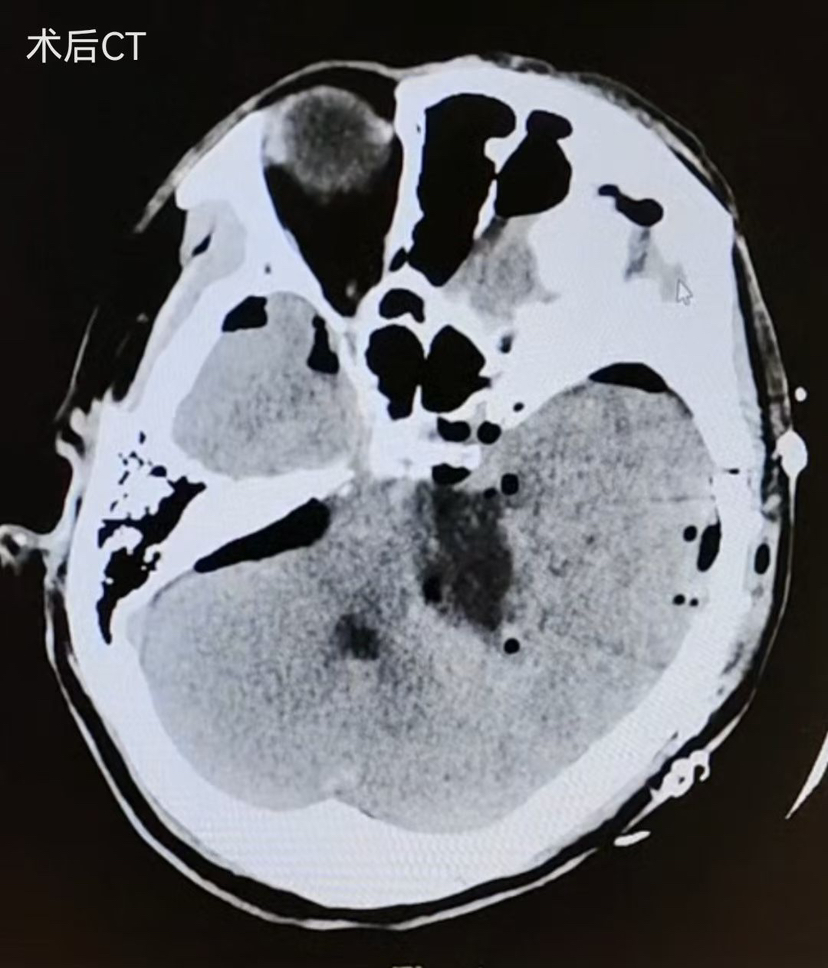

术后6hCT